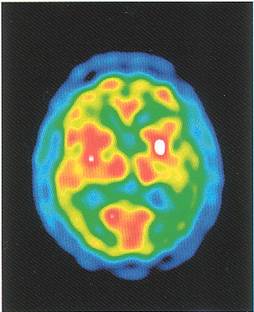

Ved scanning af hjernen aftegner man hjernens struktur, altså hvordan den ser ud. Dette gøres ved at optage snitbilleder af hjernen, enten ved hjælp af computer røntgenundersøgelse, CT-scanning, som er en standardundersøgelse ved demensudredning, MR-scanning, som er en kombineret anvendelse af magnetfelter og radiobølger, og endelig SPECT- og PET-scanning, som er en undersøgelse hvor man aftegner hvordan hjernen fungerer. De tre sidstnævnte udføres kun sjældent, da der til alle bruges meget specielt og dyrt udstyr.